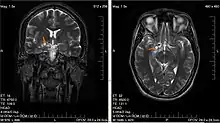

Low-grade brain glioma in a 28-year-old male. (Taken on 10 July 2007)

• Biologically benign gliomas [WHO grade I] are comparatively low risk and can be removed surgically depending on their location[50]

• Low-grade gliomas [WHO grade II] are well-differentiated (not anaplastic); these tend to exhibit benign tendencies and portend a better prognosis for the patient. However, they have a uniform rate of recurrence and increase in grade over time so should be classified as malignant.

• High-grade [WHO grades III–IV] gliomas are undifferentiated or anaplastic; these are malignant and carry a worse prognosis. Despite being classified as a high-grade glioma, infant-type hemispheric gliomas have relatively good clinical outcomes, yet they endure significant deficits, making them good candidates for therapy de-escalation and trials of molecular targeted therapy.[57]

Of numerous grading systems in use, the most common is the World Health Organization (WHO) grading system for astrocytoma, under which tumors are graded from I (least advanced disease—best prognosis) to IV (most advanced disease—worst prognosis).